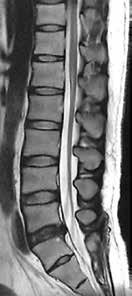

Abb. 7 a + b: LWS-Aufnahmen mit Compressed SPEEDER zur Beschleunigung und AiCE zur Rauschentfernung; Abb. 8: Menü zur Aktivierung von AiCE im InLine-Postprocessing-Menü: A Aktivierung von AiCE oder einem anderen Filter; B + B1 Einstellung des Einblendungsfaktors d01–d05; C + C1 Anpassung des Rauschniveaus; D Aktivierung des Kantenanhebungsfilters.